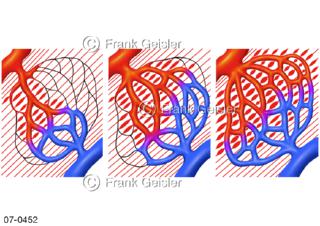

Bildergalerie Herz, Blutkreislauf

Bilder zu Herz, ein muskuläres Hohlorgan, das den menschlichen Körper durch rhythmische Kontraktionen mit Blut versorgt und dadurch die Durchblutung der Organe sichert, das Kreislaufsystem zeigt den Transport von arteriellem sowie venösem Blut durch das kardiovaskuläre System (Herz-Kreislauf-System), bestehend aus Blutgefäßen, Lymphgefäßen und dem Herz